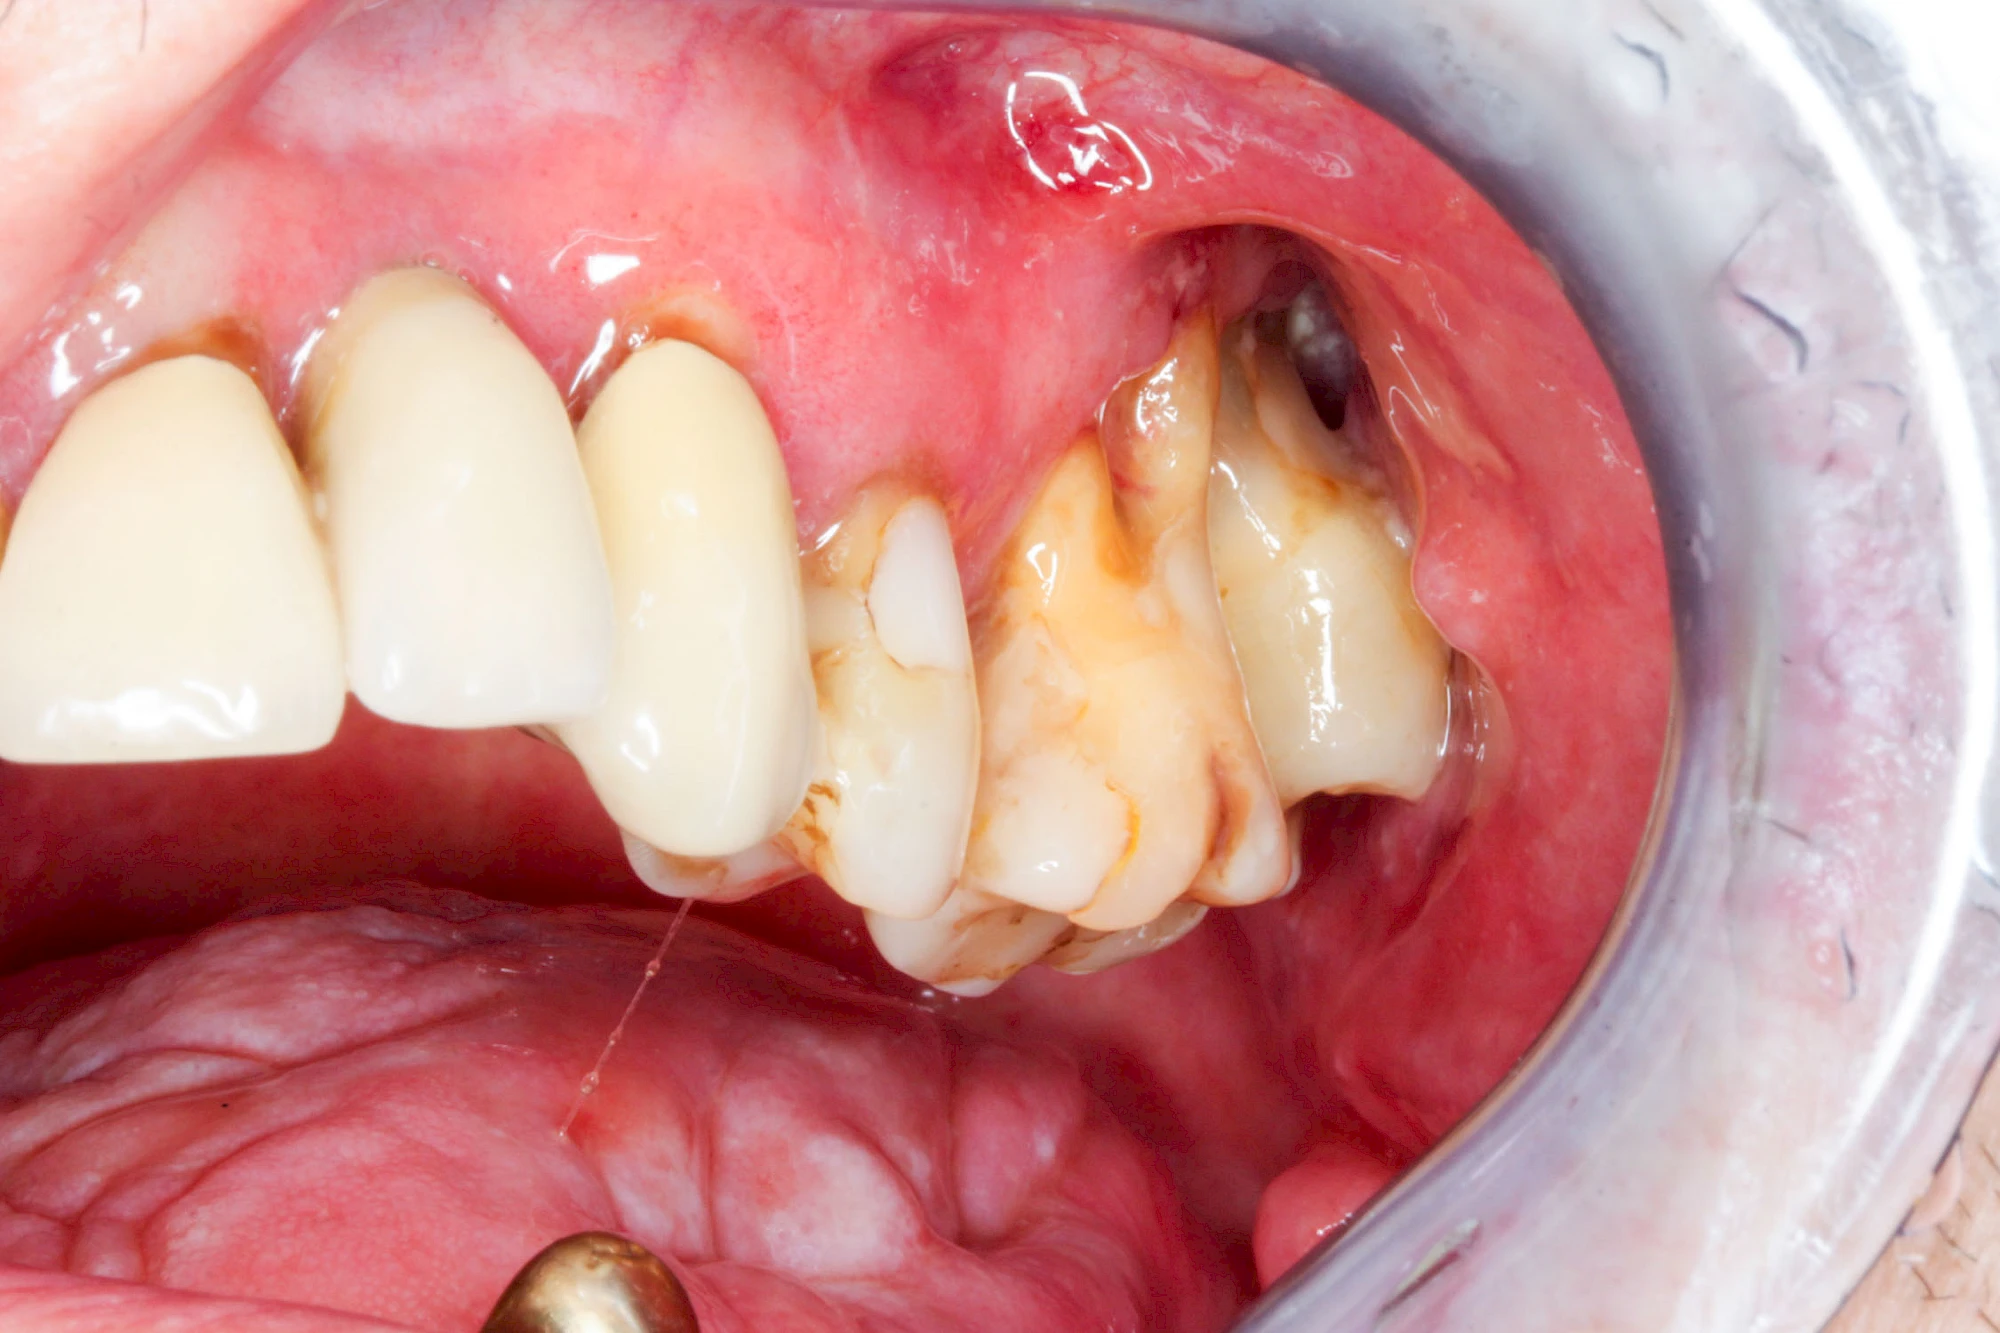

Sonderform: Fistel

Bei einer Fistel hat sich meist eine Entzündung (manchmal auch Erreger selbst) z. B. aufgrund von Karies oder aufgrund eines Unfalls über den Zahnnerv und die Wurzelspitze (Apex) in den umliegenden Knochen ausgebreitet (apikale Parodontitis) und schnell einen Weg durch den umgebenden Knochen und die aufliegende Schleimhaut in die Mundhöhle gebahnt.

Fisteln sind in der Regel nicht schmerzhaft und fallen häufig als kleine Öffnung weiter entfernt vom Zahnfleisch nahe der Umschlagfalte auf. Aus der Fistelöffnung entleert sich spontan gelbliches Sekret (Eiter) oder es lässt sich mit dem Finger ausstreichen. Manchmal beschreiben die betroffenen Menschen immer wieder einen komischen Geschmack im Mund.

Im fortgeschrittenen Stadium kann die Schleimhaut sich weiter zurückgezogen haben und die Wurzelspitze sichtbar sein. In der Regel treten bei Fisteln keine Schwellungen auf, weil sich die Entzündung nicht im Gewebe ausbreitet.